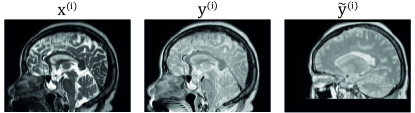

Assume we have a paired training set of input images and non-aligned target images . Following the notation by Kong et al. [32] we denote the (unavailable) aligned ground truth targets by . Furthermore, unknown deformations connect the coordinate systems of the inputs and the targets.

For the experiments we used CERMEP-IDB-MRXFDG data set which is freely available for research use [41]. The data set consists of 37 rigidly registered CT and T1 MRI head scan pairs. We resampled all the images to the MRI-resolution of . Pre-processing of the T1 images was similar to the one done for the cross-modality MRI synthesis data set as we applied N4 bias correction [53] using Advanced Normalization Tools (ANTs) software [5] and normalized the brain white-matter to the mean value of one using the implementation by Reinhold et al. [46] together with the implementation by Iglesias et al. [21] for brain mask extraction. We additionally removed any external objects from the CT images using series of morphological operations. While the skull and brain regions are relatively rigid, the image volumes extend to neck region with significant registration mismatches as can be seen in Figure 5. We divided the data set to cases for training, for validation, and for testing.